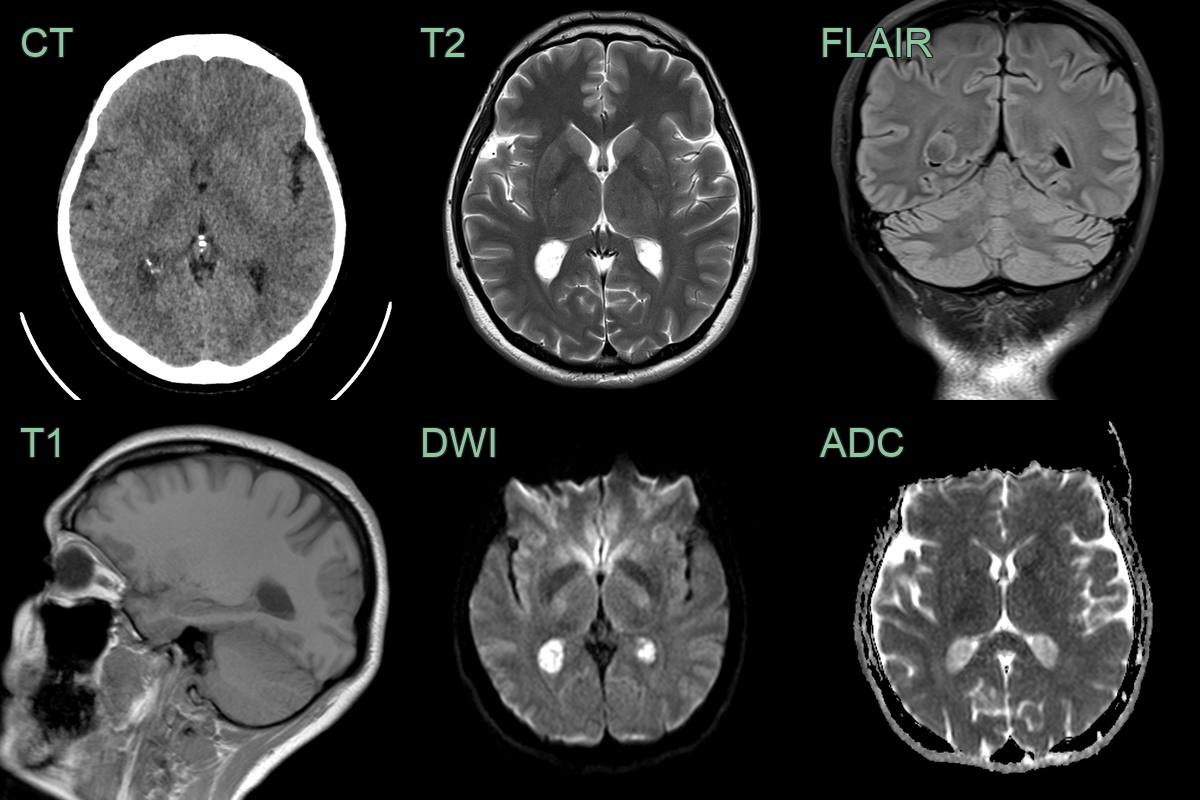

Choroid plexus xanthogranuloma

• The choroid plexus within the trigones of the lateral ventricles were expanded and hyperintense on diffusion-weighted imaging.